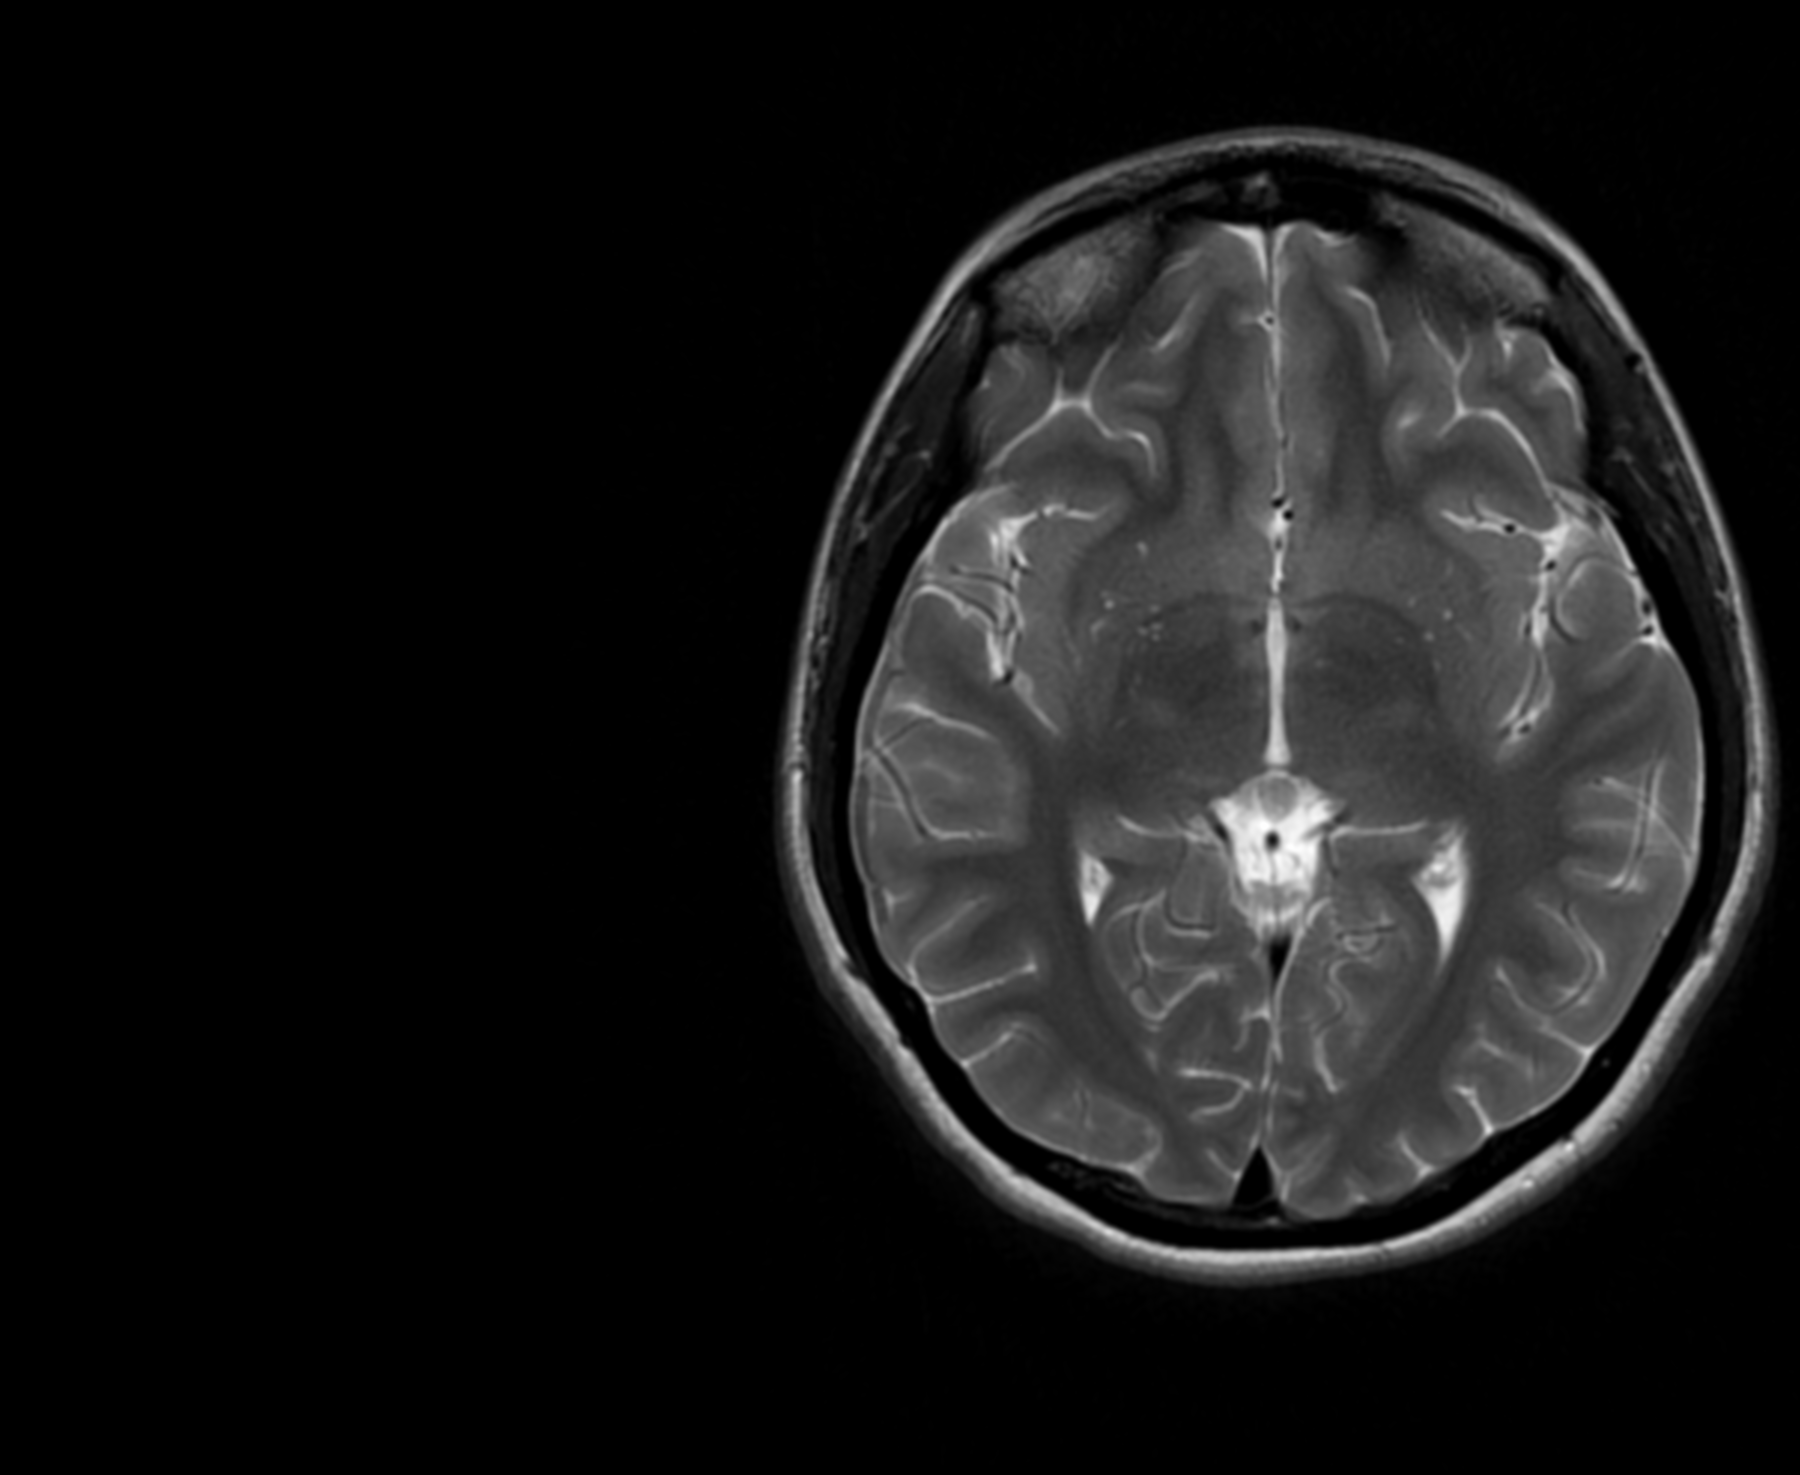

My mum worried it was a tumour (and as a nurse, her worry was hard to get). After an MRI scan, a four-day hospital visit, many tried and failed medications, I was diagnosed with chronic migraines on New Year’s Eve 2020; a neurological condition I may have to live with for the rest of my life.

But my chronic state was different (chronic migraines are classified as someone who has more than 15 headache days a month). It didn’t present like my previous migraines had. I had no aura, there were times I didn’t even have a headache. Instead, I was mainly suffering from nausea, vomiting, vertigo. My GP prescribed me a cocktail of drugs, none worked, and after a month of constant calls and visits, my doctor referred me for an MRI scan. It was all clear, but I still had no answer.

My doctor grew so concerned she called the hospital and got me on the list to see a medical consultant. But this was late December 2020, the hospitals were busy, and something went wrong with my referral. I wasn’t on any list. So, after a long wait, an A&E doctor saw me. The difficulty is, while I felt terrible on the inside, compared to everyone else in A&E, I looked fine. Migraines are invisible; they don't even show on scans. The A&E doctor asked if I’d drunk enough water. I said yes, a month into headaches and vomiting, I had made sure I was hydrated.

Due to the stroke-like symptoms of her migraines, Kim worried every attack was another stroke. She was sent back and forth to the stroke unit, and had several CT and MRI scans, which revealed nothing. Her doctor said the headaches were just side effects of the stroke and kept sending her home.

It took Lisa having a migraine seizure while on holiday in Dubai in 2019, for her doctors at home to listen. In the final days of her holiday, the left side of Lisa’s face completely dropped, she lost vision in her left eye, and was hospitalised for two days. Doctors feared she’d suffered a stroke and sent her for an MRI. Upon returning to the UK, Lisa’s doctors revealed years of migraines had caused significant scarring on the left-side of Lisa’s brain.

- All MRI pictures featured are my own.